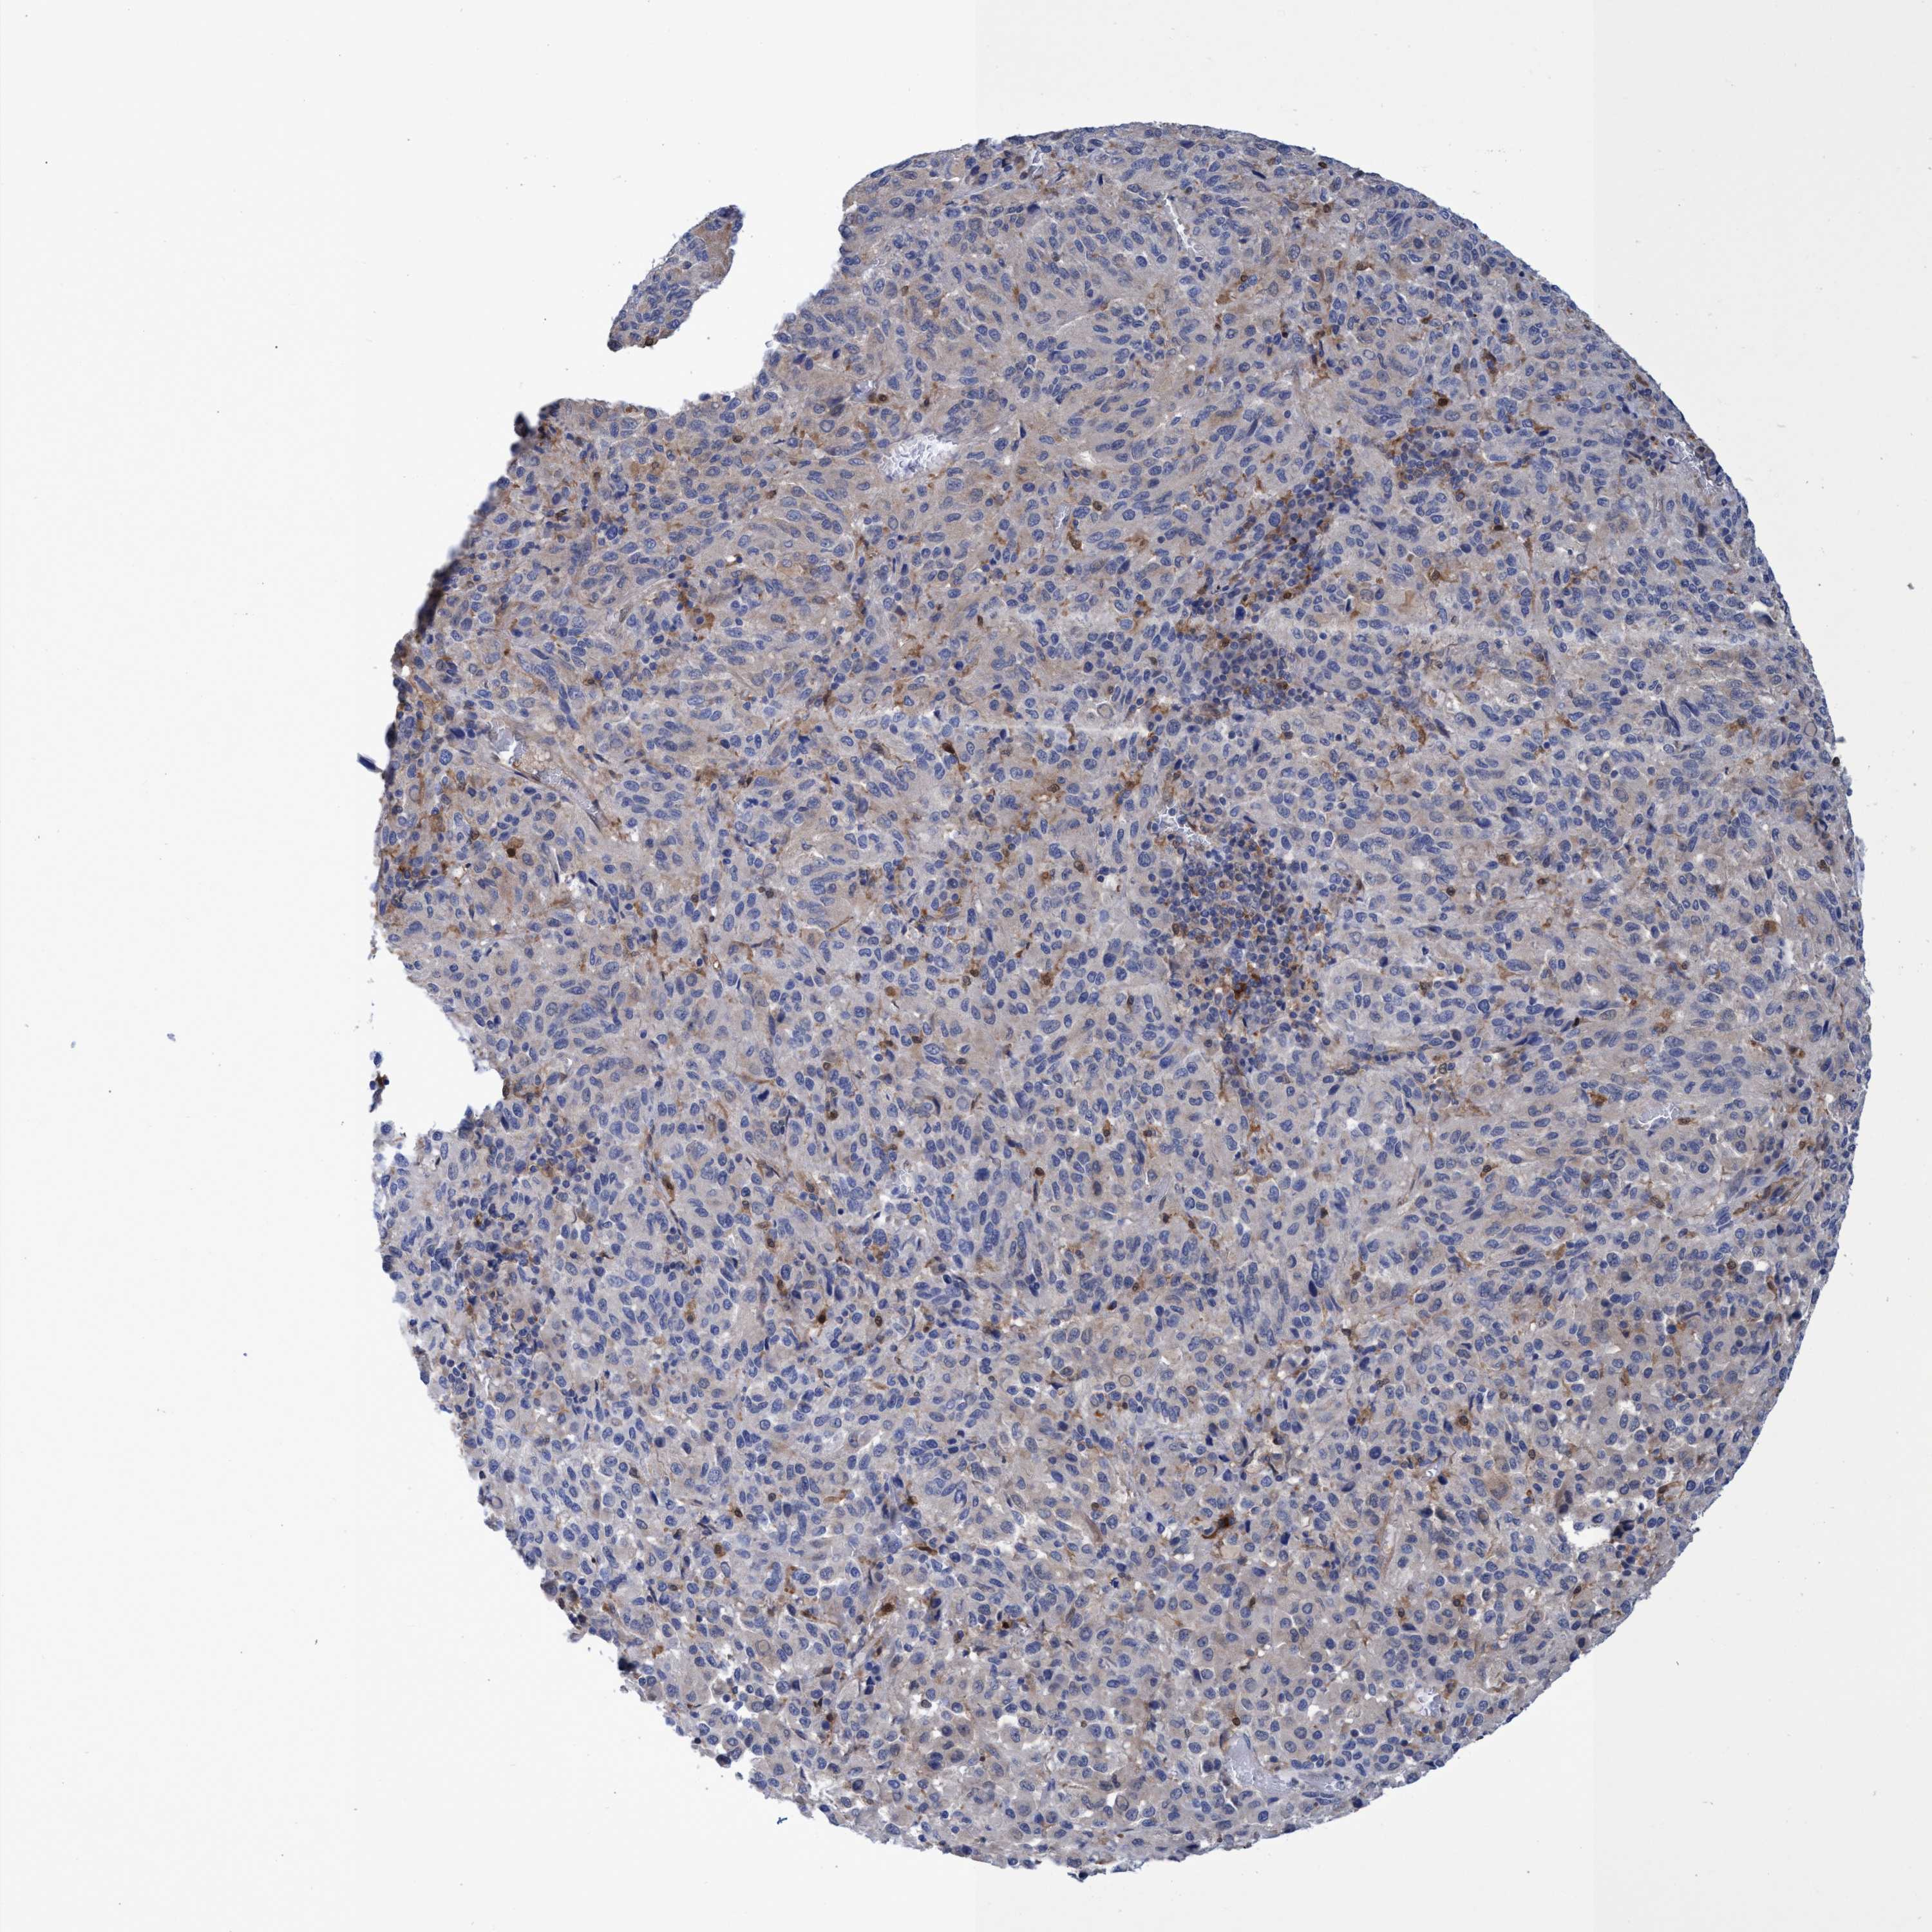

MELANOMA - Protein expressioni

A mouse-over function shows sample information and annotation data. Click on an image to view it in a full screen mode. Samples can be filtered based on level of antibody staining by selecting one or several of the following categories: high, medium, low and not detected. The assay and annotation is described here.

Note that samples used for immunohistochemistry by the Human Protein Atlas do not correspond to samples in the TCGA dataset.

Antibody stainingi

Antibody staining in the annotated cell types in the current human tissue is reported as not detected, low, medium, or high, based on conventional immunohistochemistry profiling in selected tissues. This score is based on the combination of the staining intensity and fraction of stained cells.

Each image is clickable and will lead to virtual microscopy that enables deeper exploration of all samples and also displays staining intensity scores, fraction scores and subcellular localization as well as patient and tissue information for each sample.

Antibody HPA023204

Antibody HPA027776

Staining

High

Medium

Low

Not detected

Intensity

Strong

Moderate

Weak

Negative

Quantity

>75%

75%-25%

<25%

None

Location

Nuclear

Cytoplasmic/membranous

Cytoplasmic/membranous,nuclear

Malignant melanoma, NOS

Malignant melanoma, Metastatic site